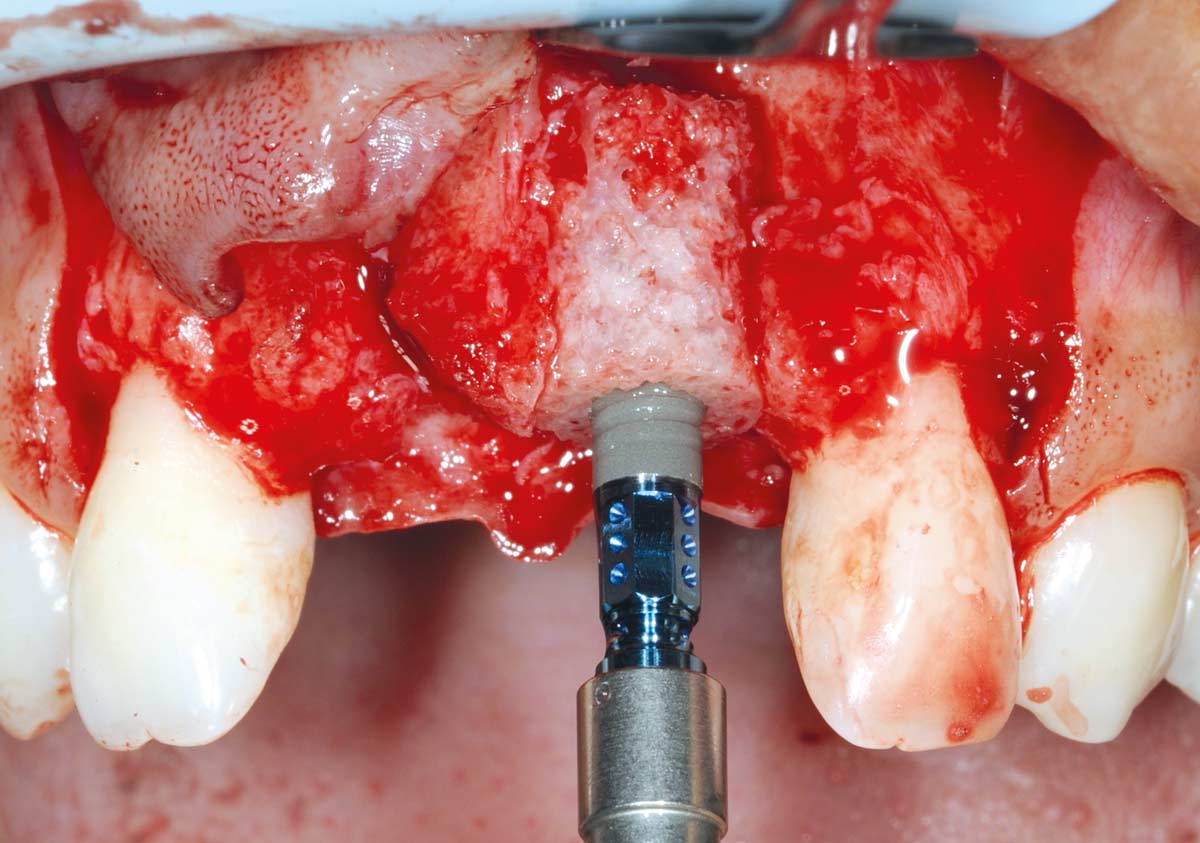

10/26 - Fixation of maxgraft® bonering with a Straumann® SLActive Bone Level Tapered ImplantBone augmentation in aesthetic zone with maxgraft® bonering - Dr. A. Patel

11/26 - Implantation in region 11Bone augmentation in aesthetic zone with maxgraft® bonering - Dr. A. Patel